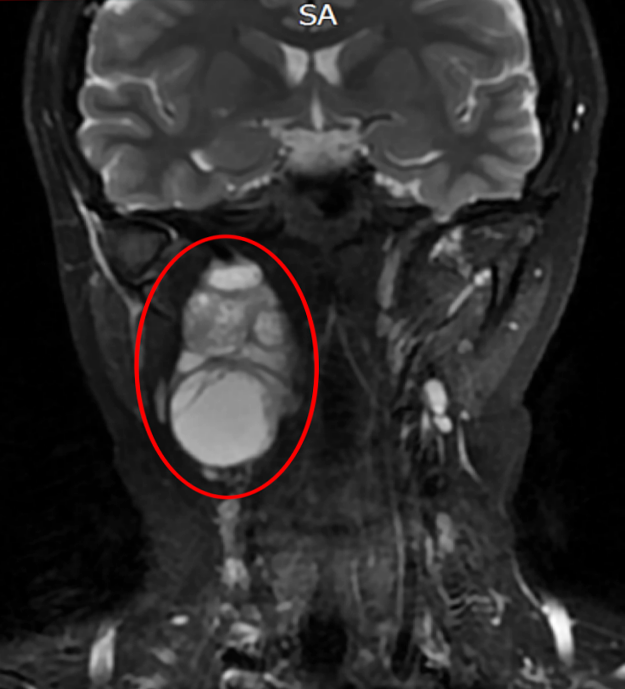

29岁的肖女士(化名)4个月前无意中发现右侧颈部出现一核桃大小包块且持续增大。经超声检查提示右侧颌下囊实性肿块,结合详细体格检查,耳鼻咽喉科团队初步判断肿瘤位于解剖结构极为复杂的咽旁间隙。该区域是颈内动脉、颈内静脉、迷走神经、舌下神经、副神经、舌咽神经等重要结构的密集交汇区。

在充分的术前准备与麻醉科的精准配合下,手术由耳鼻咽喉科副主任彭炜主刀进行,姚伟、张道行主治医师担任助手。术中探查证实了术前预判,肿瘤深藏于颈部重要结构之间,并与神经关系紧密,舌下神经瘤化,迷走神经部分受累。

手术团队在显微镜辅助下,凭借毫米级的精细操作,小心翼翼地辨识、分离,离断舌下神经,后成功将肿瘤从迷走神经血管上完整剥离,实现了肿瘤全切与神经功能保护的双重目标。